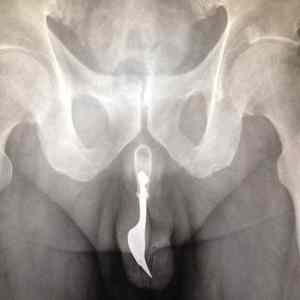

Primitive birth control. (Keeps unwanted "predators" out)

GO FORK YOURSELF!